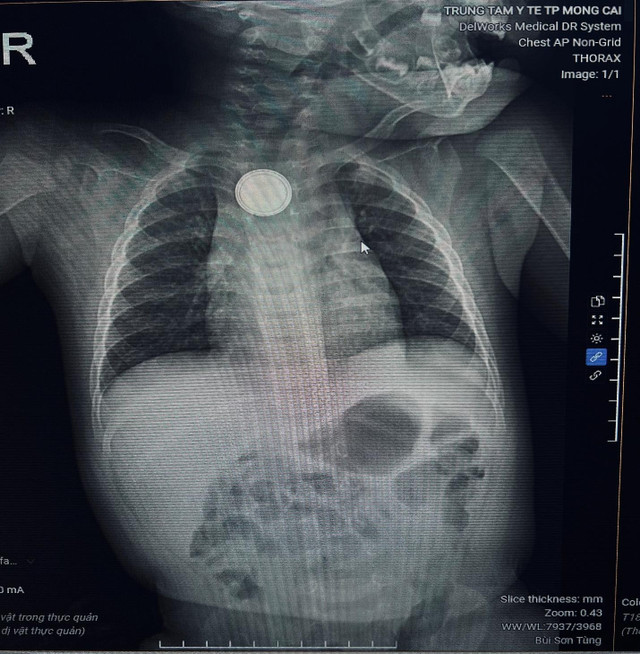

Trung tâm Y tế Móng Cái (Quảng Ninh) vừa tiếp nhận cấp cứu bệnh nhi B.M.K. (11 tháng tuổi) nhập viện trong tình trạng nôn nhiều, quấy khóc dữ dội. Qua thăm khám và chụp X-quang, các bác sĩ phát hiện dị vật kim loại hình tròn mắc kẹt tại thực quản.

Bệnh nhi được chỉ định nội soi cấp cứu, phát hiện dị vật là một viên pin cúc áo. Các bác sĩ nhanh chóng lấy dị vật ra an toàn, tuy nhiên niêm mạc thực quản của trẻ đã bị tổn thương do phản ứng ăn mòn điện - hóa học. Hiện bệnh nhi đang được điều trị tích cực và theo dõi biến chứng.

Hình ảnh chụp Xquang phát hiện dị vật thực quản/ Ảnh Trung tâm Y tế Móng Cái